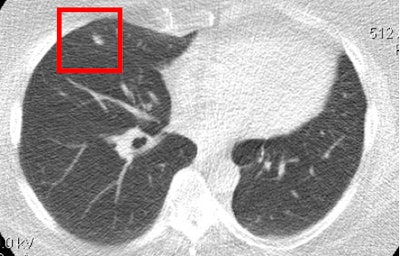

Lung cancer is clearly visible in the ultralow-dose CT image above but cannot be seen in the chest radiograph of the same patient below. All images courtesy of Dr. Waël Hanna.

Among the 311 patients enrolled, 1,096 pairs of x-ray and MDCT scans were analyzed, Hanna said. CT was significantly more sensitive than radiography (94% versus 21%, p < 0.0001) for the diagnosis of new or recurrent lung cancer. CT also had a higher negative predictive value than x-ray (99% versus 96%, p = 0.007).

There were new or recurrent lung cancers in 63 patients: 78% were asymptomatic and the cancer was detected only at CT. Two-thirds of these asymptomatic patients were diagnosed within the first year and 26% within the second year, Hanna said.